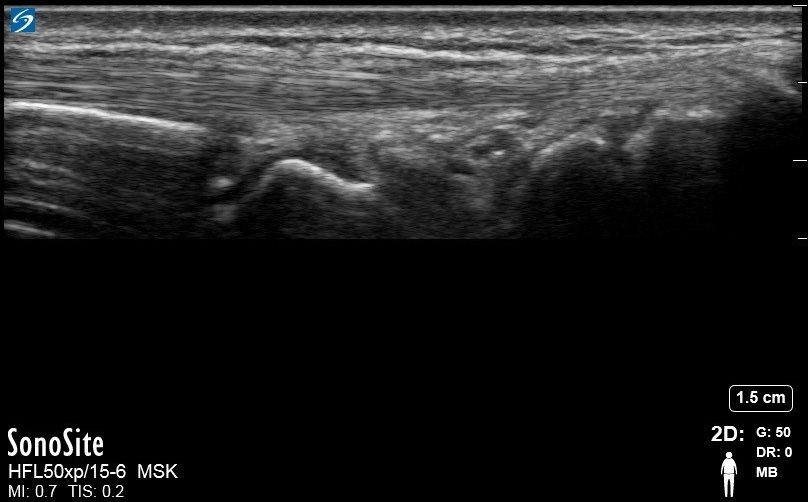

Wrist Extensor Carpi Radialis Brevis and Extensor Carpi Radialis Longus 1 Image